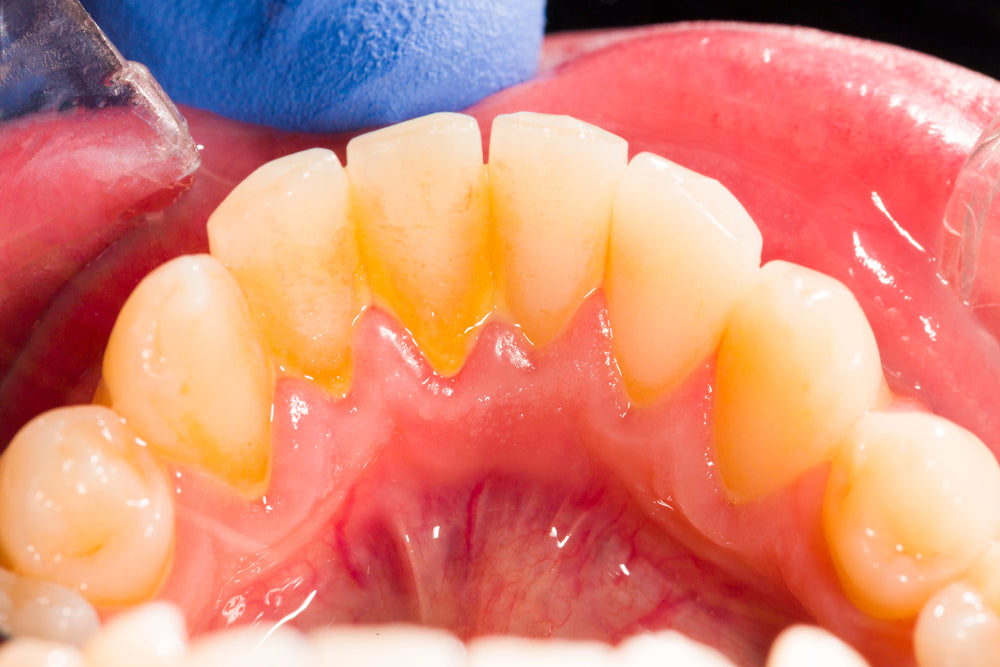

plaque on teeth

www.DepositPhotos.com